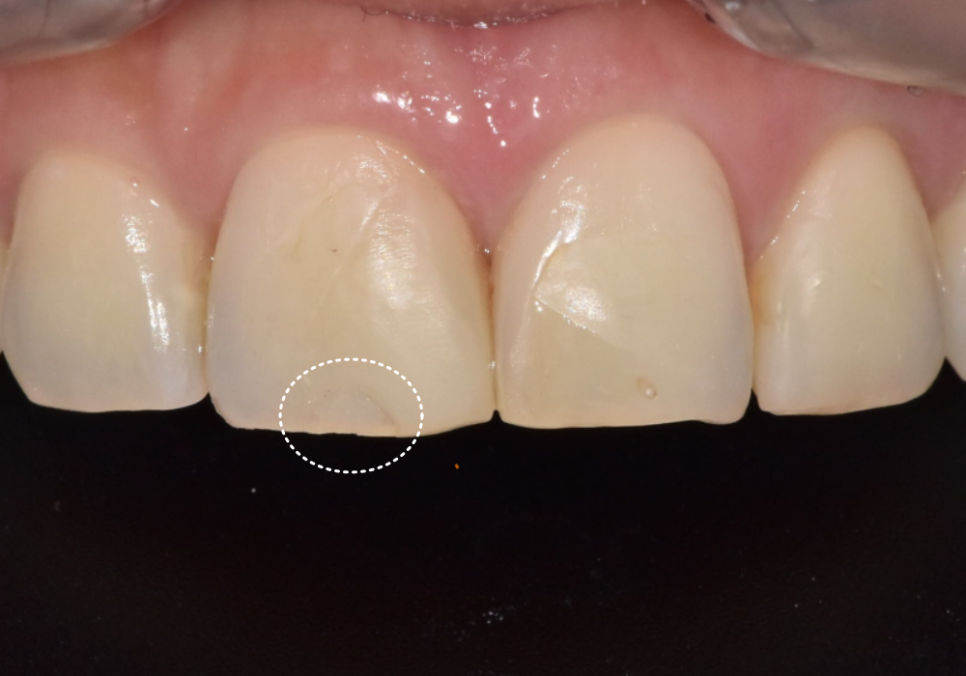

이 환자분은 예전에

앞니 사이가 벌어져 보여서

레진으로 공간을 메우는 치료를 받으셨습니다.

그런데 1년 정도 지나고 나니

레진을 붙였던 부위가

갈색으로 비쳐 보이기 시작했다고 하셨어요.

하지만 여기서 가장

중요하게 살펴봐야 할 점은,

단순한 레진 변색인지,

아니면

2차 충치가 숨어 있는 것은 아닌지를

정확히 판단하는 것입니다.

먼저 방사선 사진으로 확인해보니

다행히 2차 충치가 뚜렷하게 보이거나,

문제가 있어 보이지 않았습니다.